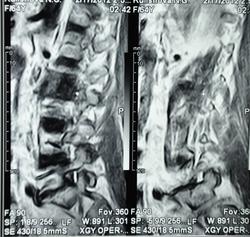

Можно гадать, но без клиники и анамнеща никак. Исходя из картинок больше на пиогенный вроде. Хотя, и тубер может выглядеть так же.

Наверное, правильнее это можно назвать спондилодисцитом ( не туберкулезной этиологии)

Как-то  ( боюсь повториться, но что делать!) наш преподаватель по рентгенологии в Хабаровске говаривал:"Если больного принесли на носилках из-за невозможности движений, то это  пиогенныый ( гематогенный) спондилит, если пришел сам, на своих ногах, то туберкулезный."Еще нас учили, что размеры деструкции в одном позвонке при гематогенном поражении больше, чем в следующем позвонке, при туберкулезном-2 и более позвонка поражены одинаково;реактивный склероз  чаще встечается при гнойных процессах, при туберкулезе-как правило, не бывает; процесс при туберкулезе протекает медленнее,при гематогенном-может молниеносно ;наличие туберкулеза  других органов и систем ( не обязательно).

Мне видится здесь последствия зверского дисцита.  Предположу, ситуация не острая - данных за отек соответсвующих позвонков нет, хотя для убедительности нужен FatSat.  Из этого делаем вывод- на первое место исход воспаления, с формированием кистозных изменений, на второе - быть может нечто постравматическое с последующим, опять же, дисцитом.

При пункция патологического участка позвоночника - Лимфома позвоночника. Передан онкологам на лечение.

Уважаемый Николас, диагностировать лимфому по представленным сканам-высший пилотаж.Аксиалы, короналы напрочь отсутствуют-как можно обнаружить паравертебральный мягкотканный компонент ( если он имеет место быть, конечно)????.А вот явные признаки спондилодисцита имеются.

По мне так спондилодисцит. Характерный жидкостной сигнал в диске, деструкция смежных позвонков. А уж какой этиологии, это пусть клиницисты решают.